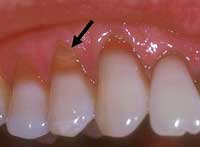

Забна ерозија

Забната ерозија се дефинира како процес на неповратно губење на тврдите забни ткива како резултат на хемиски случувања кои не вклучуваат бактериска активност. Овие хемиски процеси главно се состојат во растворање на минерализираните ткива на забите поради контакт со киселини.

o Абфракција – губење на забната површина во пределот на забните вратови (до непцето) како резултат на механички стрес поради делување на силите на истегнување и притисок при процесот на џвакање